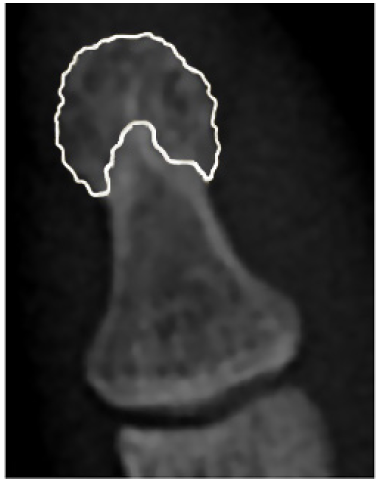

Se considera que el PFDM es el área de la falange distal en la que la cortical deja de ser completamente lisa y adquiere un aspecto lanceolado 15. En la Figura 1, el color blanco demarca el área correspondiente al PFDM. Otras alteraciones del PFDM descritas en radiografía simple de individuos con diagnóstico de psoriasis con o sin criterios de APs son las erosiones y la esclerosis. Estos hallazgos también han sido descritos en individuos con AR 16-18.